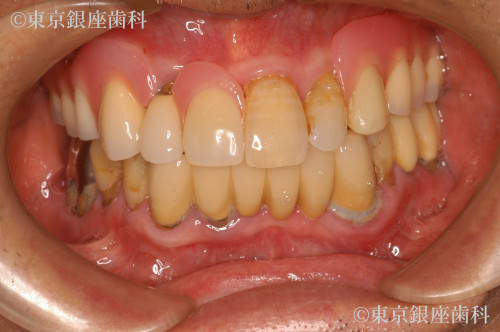

重度歯周病、義歯不適合による咬合障害をワンデイインプラントで改善した症例

Before

入れ歯が痛くて入れられない。噛めないので食事を丸のみにしているため胃の調子が悪い。

全体的に歯周病が進行していること、咬合改善を希望されていることから残存歯を全て抜歯してワンデイインプラントにすることにした。